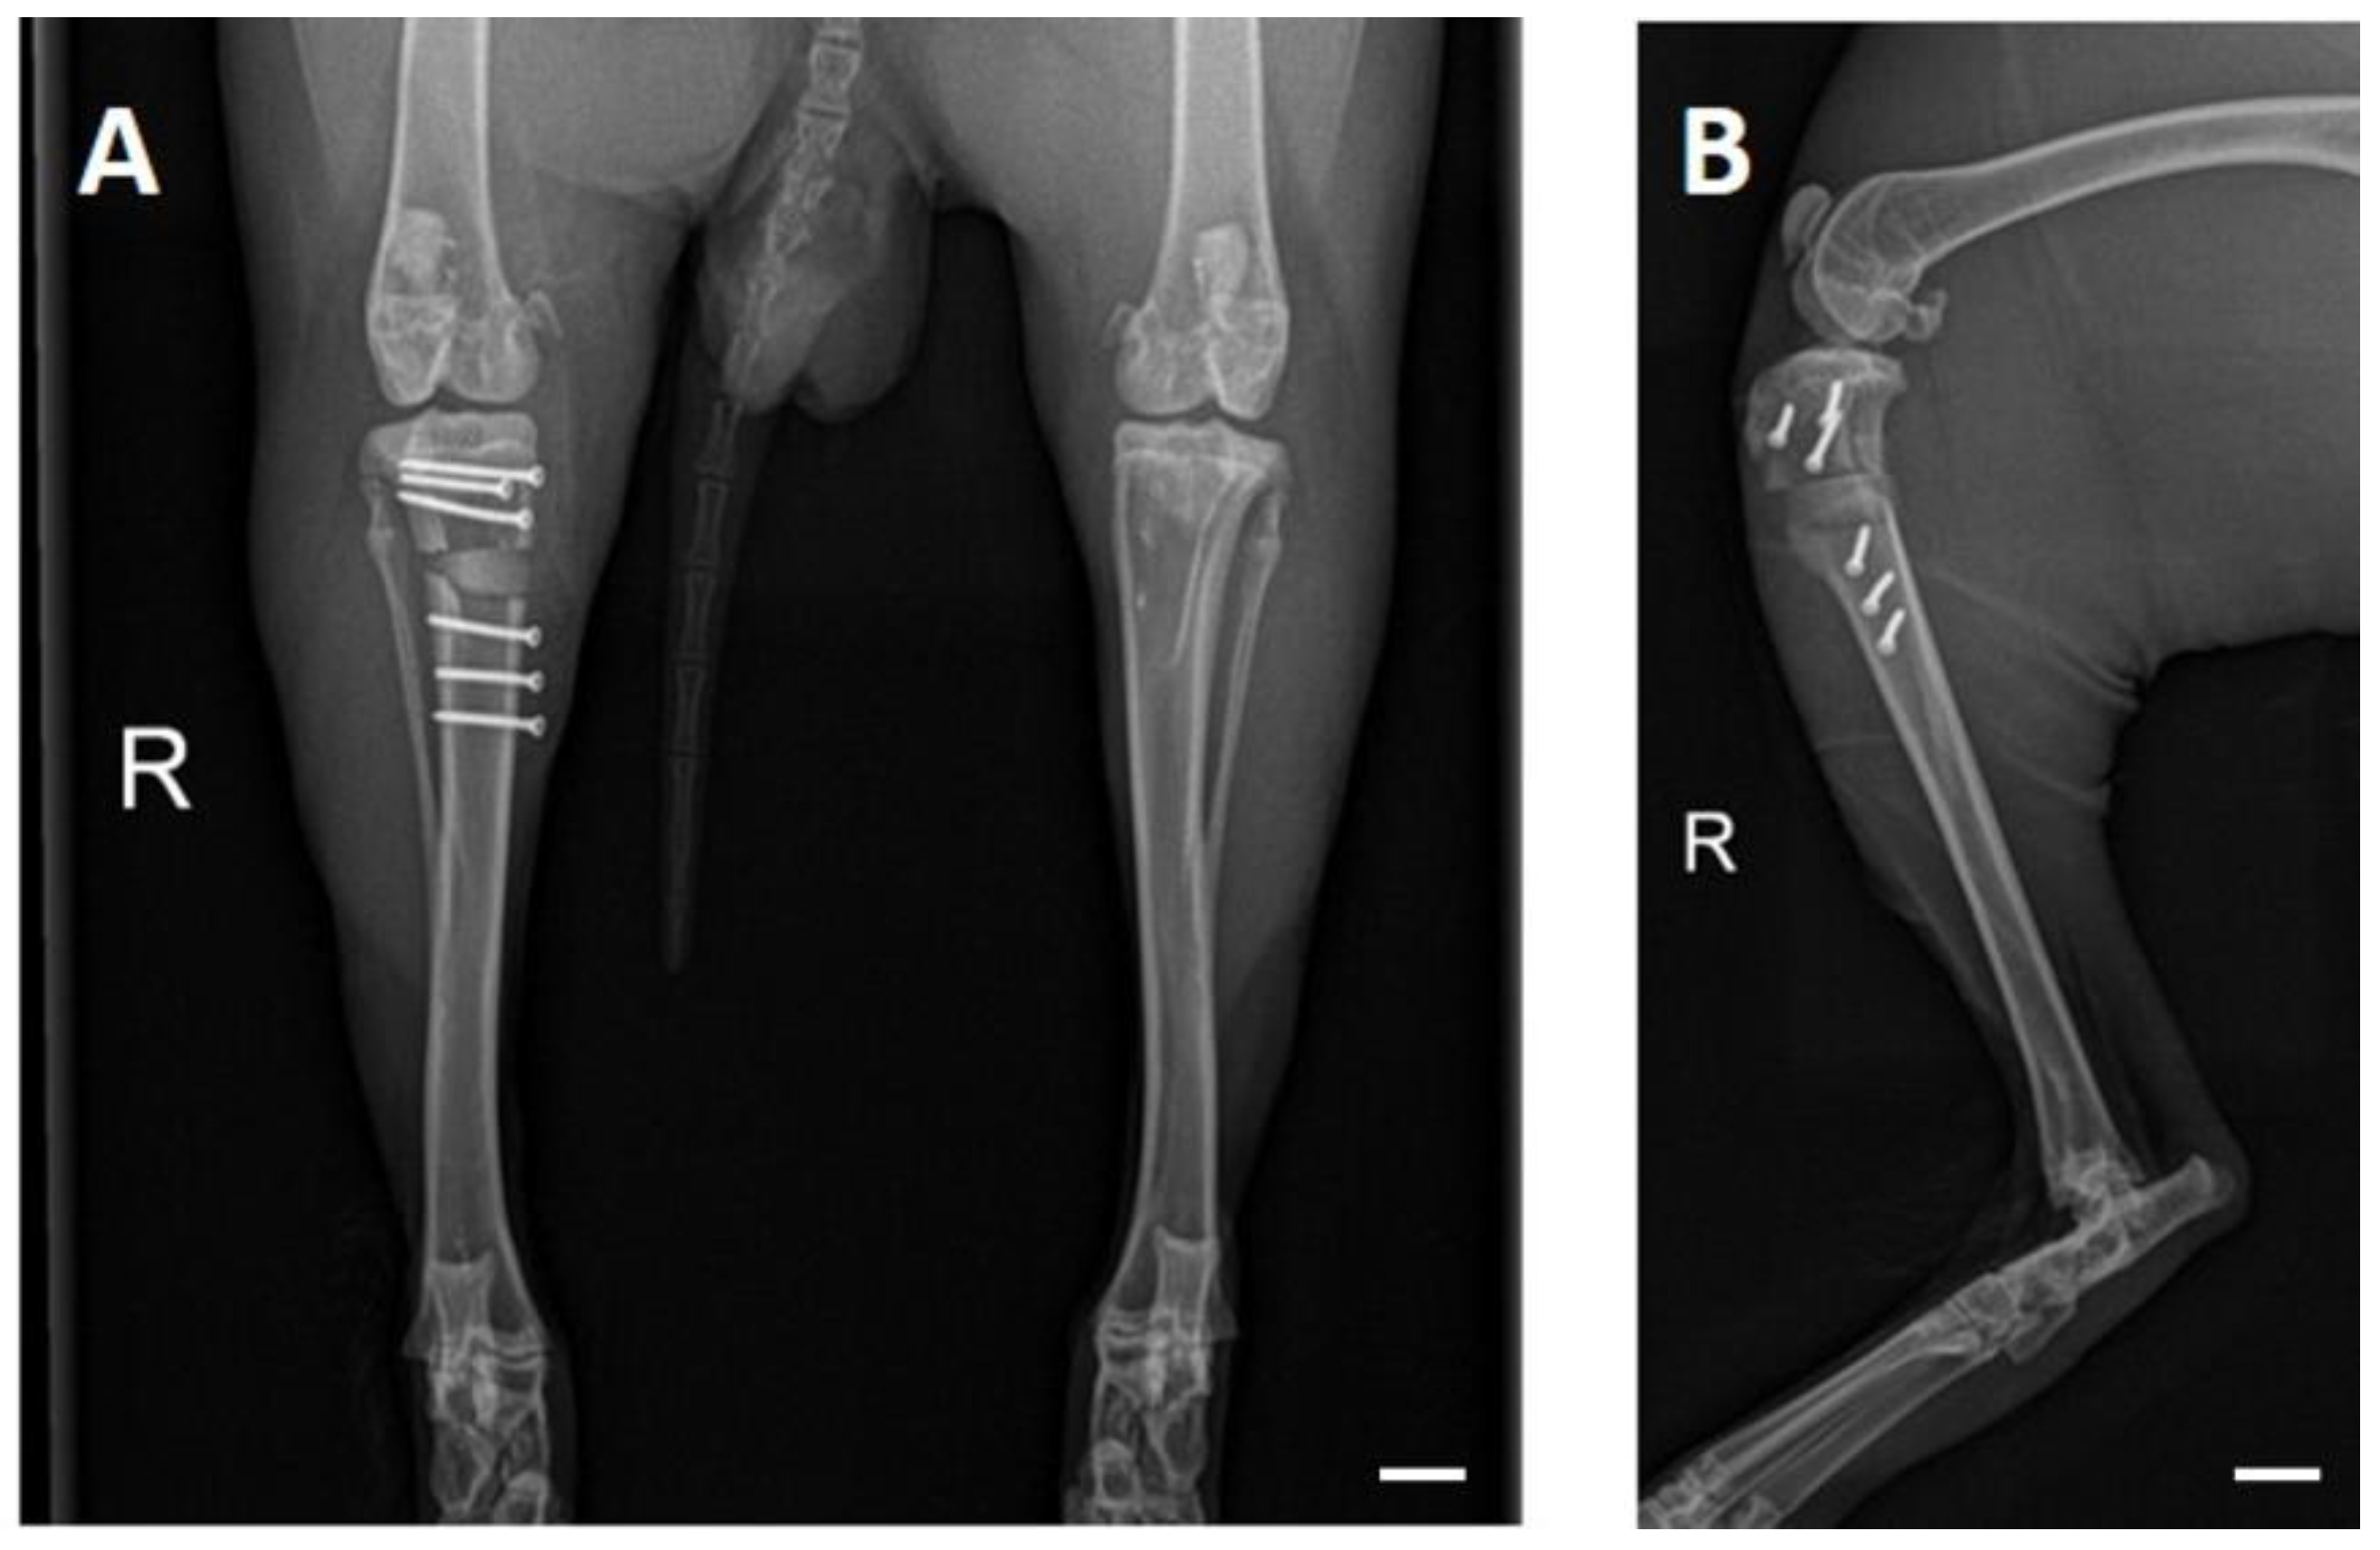

3.4. X-ray Examinations

3.5. In Vivo µCT Examinations

3.5.1. Semi-Quantitative Evaluation of the Scans